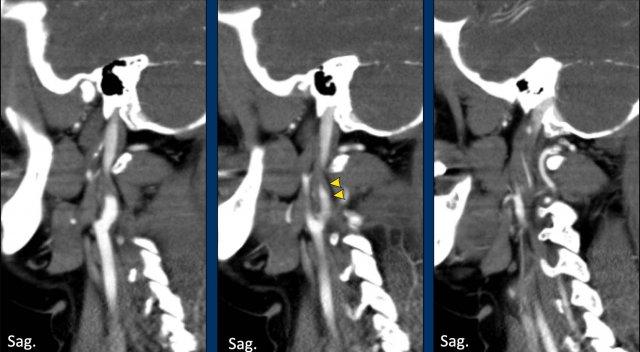

CTA vùng cổ cho thấy hình ảnh đặc trưng dạng ngọn lửa ở đoạn gần ICA, gợi ý bóc tách động mạch.

Tiếp tục xem các lát cắt ngang…

Hình ảnh lát cắt ngang cho thấy ICA trái giãn rộng với lòng mạch bị chèn ép lệch tâm.

Tóm lại, đây là trường hợp phụ nữ 35 tuổi với đột quỵ diện rộng (NIHSS = 27), tắc nghẽn động mạch cảnh do bóc tách, nhưng không có tắc nghẽn nội sọ.